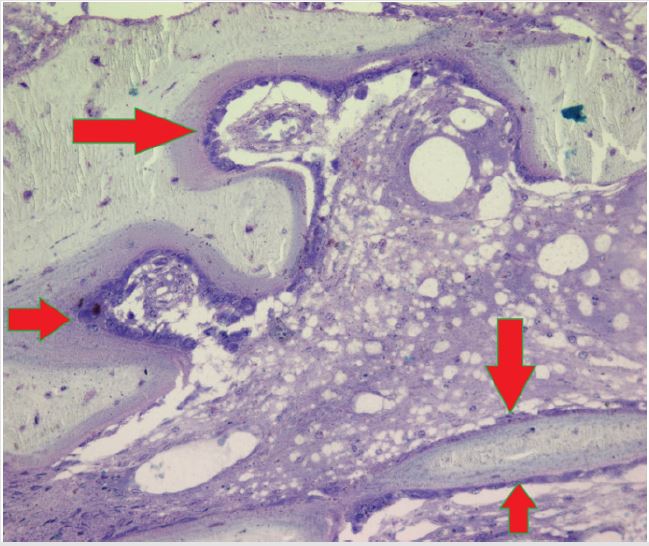

Unlike the conventional paraffin embedded biopsy sections which are thick (5-10 microns), these semi-thin sections of plastic embedded bone and bone marrow biopsies, when stained with Romanowsky stain, provide cellular morphology and structural details of the marrow in much greater detail than hitherto possible. Research conducted by the author [4-13] using the plastic embedding methods, resulted in the observation that unlike paraffin embedding (Figure 7), plastic embedded bone marrow biopsy sections the interface between the bone and marrow is well preserved (not separated) and remains intact. And as a result, the endosteal cells which line the bony trabeculae were clearly visible (Figure 8) and did not become deformed or displaced as they would have been under conventional formalin and paraffin processing. This clear picture is close to what would be observed in vivo and pointed out the significance of the endosteal region and the role of endosteal cells in the origin and the spread of leukemia [13].

Figure 8: A photomicrograph from a plastic embedded bone marrow biopsy section demonstrating complete preservation of the endosteal region. BT- bone trabecula. Thin flattened endosteal cells (arrows) that are lining the bony trabecula can be easily recognized.